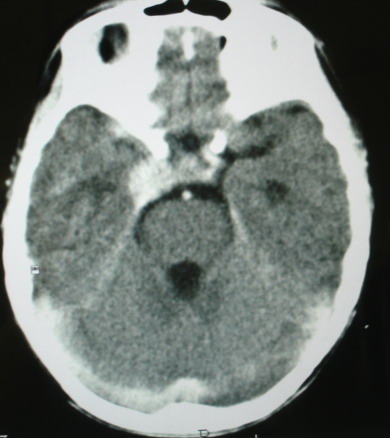

m/8y/,右侧眼睑下垂数日,发育良好,无外伤史,无头痛、恶心、呕吐,学习成绩良好。

ct意见:1、颅内血管畸形。2、右侧海绵窦血管瘤(颈内动脉海绵窦段动脉瘤)。3、脑萎缩。4、建议mr或dsa.

增强片

考虑右侧海绵窦瘘,

海绵窦瘘.注意眶内静脉有扩张.

右侧海绵窦血管瘤伴右侧海绵窦漏形成(由于右眼上静脉较左侧增粗。故考虑)。

支持 右侧颈内动脉海绵窦瘘.注意眶内静脉有扩张.